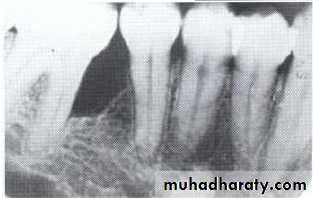

Hypodontia

Oligodontia

Anadontia

Developmental absence of all maxillary premolars and both mandibular second premolars. Note the retention of the maxillary primary canine as a result of the posterior position of the maxillary permanent canine.